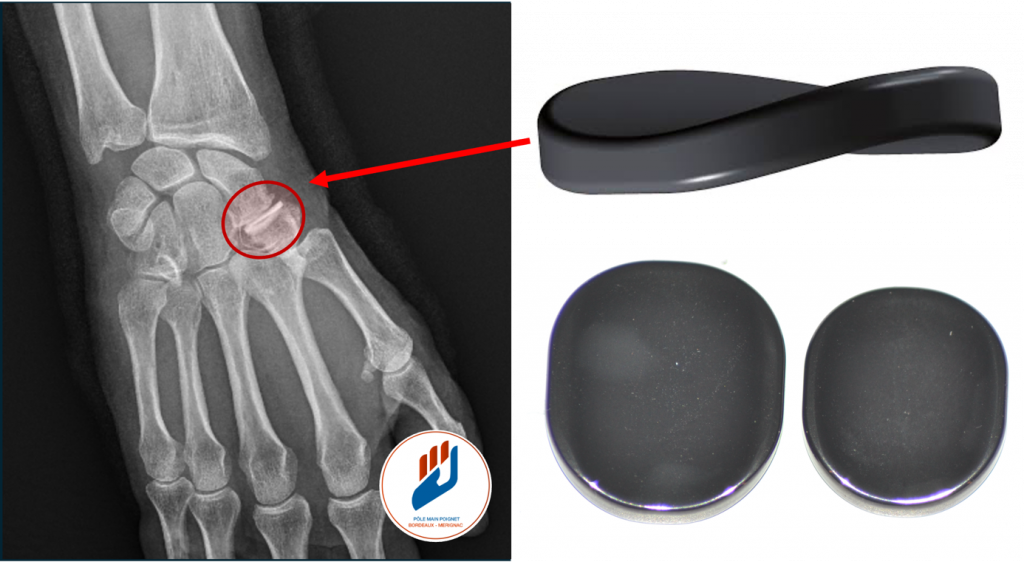

Prothèse en pyrocarbone : Le pyrocardan

L’implant pyrocardan est une solution moderne et validée. Ce matériau, initialement développé pour la chirurgie cardiaque, est très bien toléré par l’organisme. Il présente un module d’élasticité proche de celle de l’os, ce qui permet de mieux répartir les charges et de préserver les articulations voisines. Interposé entre le scaphoïde et le trapèze-trapézoïde, l’implant agit comme un coussin mécanique, supprimant la douleur tout en conservant la mobilité et la force du poignet.

Les patients opérés rapportent une nette diminution des douleurs, une amélioration de la force de préhension et une reprise rapide de leurs activités. Le risque principal, rare, est le déplacement de l’implant si la préparation osseuse est incomplète. Contrairement à l’arthrodèse, cette technique conserve la souplesse du poignet et limite l’apparition d’arthrose secondaire.

Au Pôle Main Poignet Bordeaux Mérignac, nos chirurgiens sont spécialisés dans la pose du Pyrocardan, une intervention qui demande une formation spécifique et une expertise particulière.